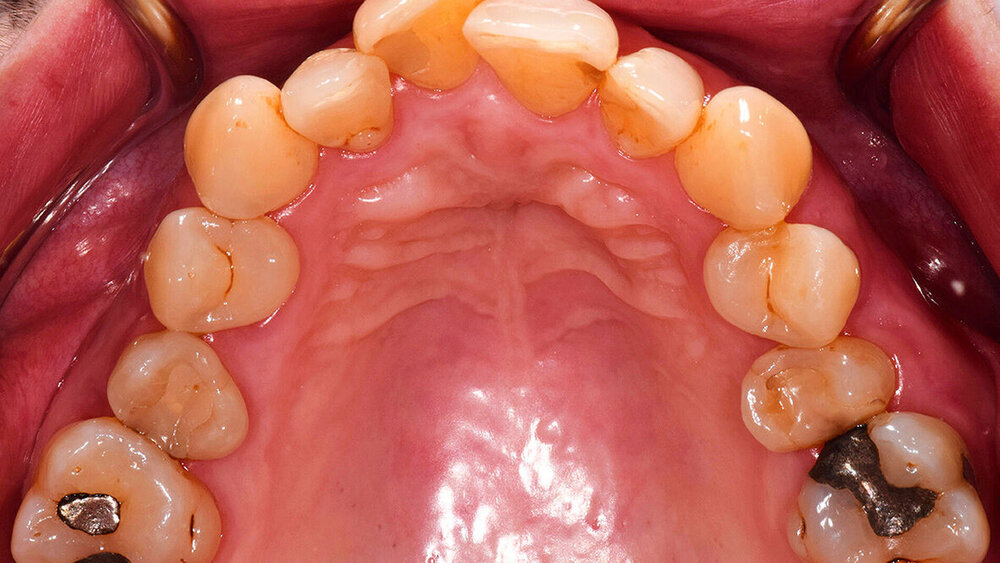

Es lagen Gelenkgeräusche und eine Deviation bei Mundöffnung bei ansonsten unauffälligem extraoralem Befund vor. Die Schleimhäute waren ohne pathologischen Befund. Es fehlten die Zähne 17, 27, 37, 47. Das Gebiss war konservierend versorgt, am Zahn 21 zeigte sich eine erneuerungsbedürftige Füllung (Sekundärkaries). Alle Zähne reagierten auf den CO2-Kältetest, Zahn 26 zeigte eine verzögerte Reaktion. Perkussionsempfindlichkeiten lagen nicht vor. Es fanden sich generalisierte harte und weiche Beläge. Die marginale Gingiva war generalisiert entzündlich verändert, an Zahn 14 entleerte sich putrides Exsudat aus der Zahnfleischtasche. Es traten Sondierungstiefen von bis zu 12 mm auf, wobei im Ober- und Unterkieferfrontzahnbereich Sondierungstiefen von maximal 4 mm vorlagen. Der maximale interdentale klinische Attachmentverlust (CAL) lag bei 13 mm (Zahn 35). Es zeigten sich Furkationsbeteiligungen von Grad II oder III an allen Molaren sowie von Grad II an einem oberen ersten Prämolaren. Eine Zahnbeweglichkeit von Grad I konnte an den Zähnen 26, 36 und 46 und von Grad II am Zahn 35 festgestellt werden.